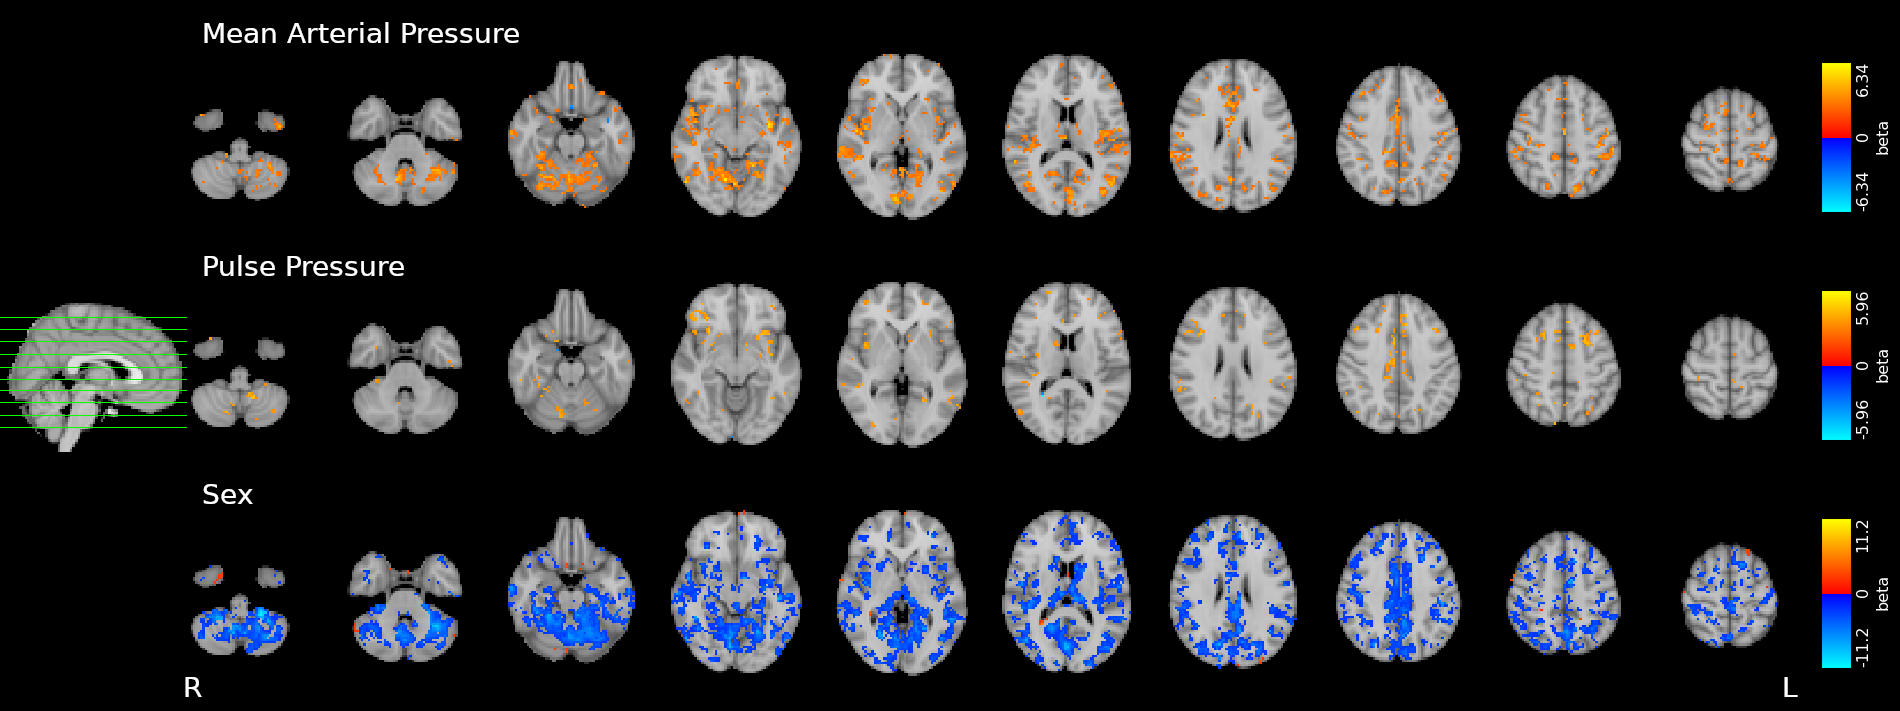

CVR and blood pressure

Due to its nature as homeostatic and cerebrovascular process, CVR is modulated by systemic changes in blood pressure¹

1. Fierstra et al. 2013 (J. Physiol.); 2. e.g. Hetzel et al. 1999 (Stroke)

Previous studies with Transcranial Doppler Ultrasound suggest to take into account blood pressure when measuring CVR²

To our knowledge, the impact of blood pressure on BOLD-fMRI based CVR estimation has not been assessed yet

We averaged the two measurements and computed the Mean Arterial Pressure (MAP) and the Pulse Pressure (PP):

Methods: effect of pressure

We used 3dLMEr¹ to set up the following LME models:

Results were thresholded at \(p<0.05\) after controlling for false discovery rate²

1. Chen et al. 2013 (Neuroimage); 2. Benjamini et al. 2006 (Biometrika)

*maps were smoothed 5mm FWHM

Methods: effect of pressure

We smooth CVR and lag maps using a dilated GM mask (white mask below) and a FWHM of 5mm (voxel size 2.5 isometric) before running 3dLMEr.

Results: blood pressure

Results: blood pressure

Results: blood pressure

Both MAP and PP should be taken into account in CVR experiments, especially in comparisons between subjects or between regions!

Results: sex

- Females show higher CVR than males in most of the GM

- Previous studies report CVR higher in females¹, in males², or no differences between the two³

- A possible cause of this difference might be related to hormonal changes during the menstrual cycle

Results: sex

Increased blood pressure

results in localised increases in CVR.

The sex of the participant can affect CVR too.

- Stationary blood pressure changes, expressed as MAP and PP, as well as sex, impact regional CVR estimation differently across sessions and subjects